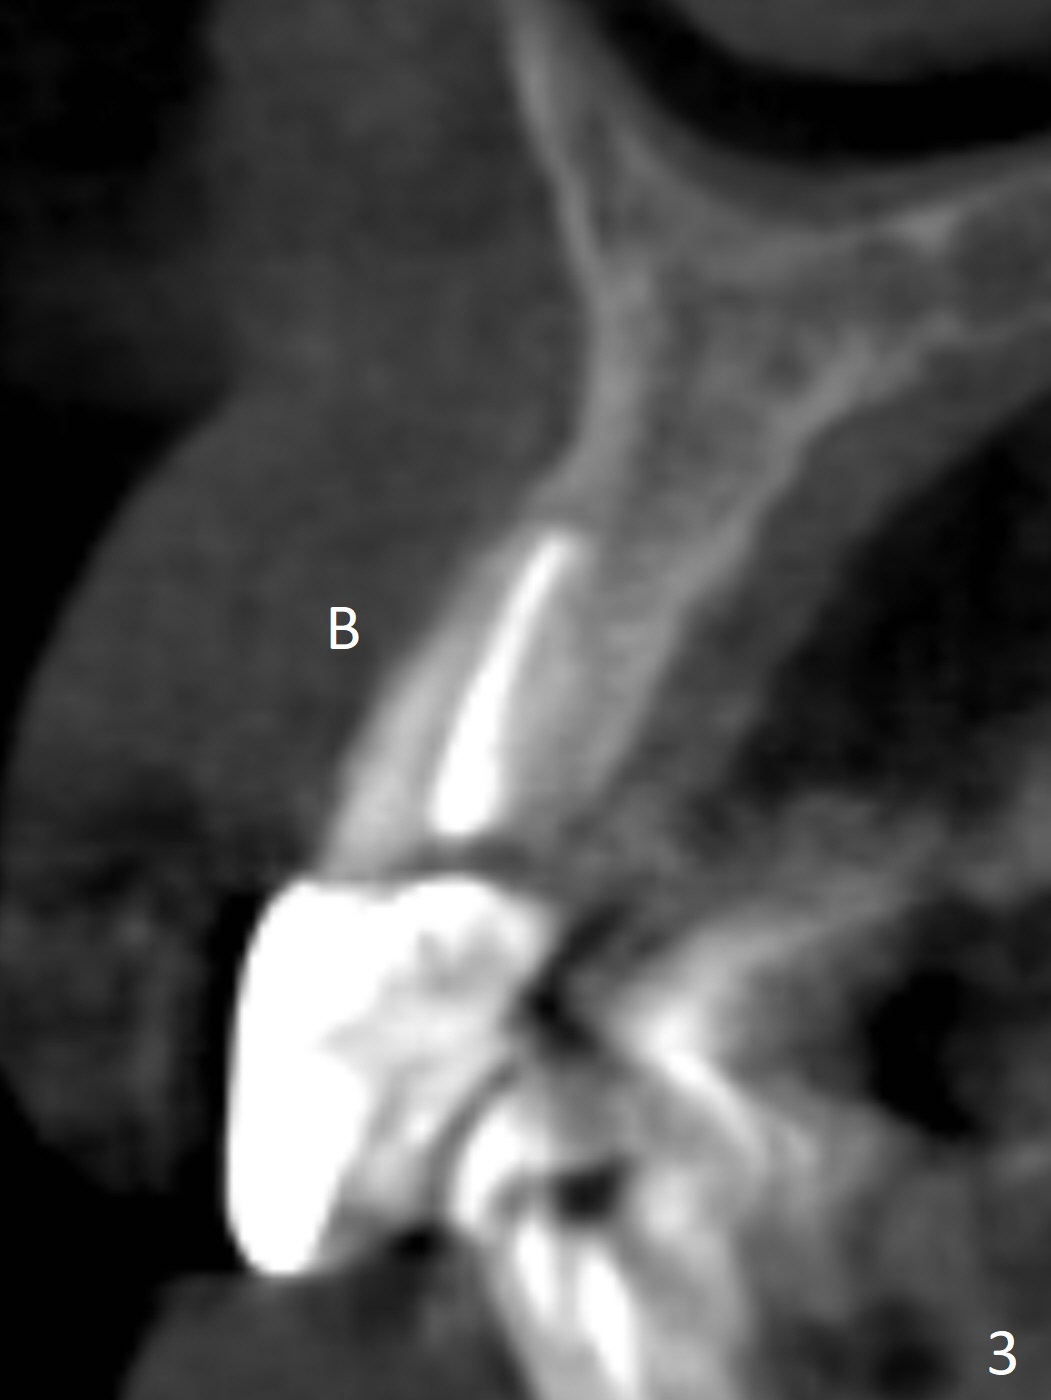

A 60-year-old man fractures the tooth #10 after implant at #7 (Fig.1). An implant should be placed in the middle of the socket at #10 since there is periapical radiolucencey at #9 and 11 (Fig.2 CBCT). The buccal plate at #10 is thin (Fig.4). A 3.8x15 mm implant (the smallest 2-piece) appears to be large for the alveolus (Fig.5). The gingiva must be thin as well. This is called thin biotype. In fact the buccal plate seems to have undergone bone resorption post 3.8x15 mm implant placement at #7. Therefore a 2.5 or 3x14 or 16 mm 1-piece implant will be placed at #10 (Fig.5). Also prepare angled ones. Take photos of #7 and 10 to show bone resorption and the thin gingiva. If the caries is not extensive, perform socket shield. In fact a 1-piece implant is chosen because of the narrow mesiodistal space.